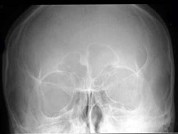

- 单项选择题男,32岁, 头晕、头痛多年,额窦X线检查如图所示, 最可能的诊断是 ( )

A、右侧额窦骨瘤

B、右侧额窦囊肿

C、右侧额窦骨岛

D、正常额窦

E、右侧额窦软骨瘤